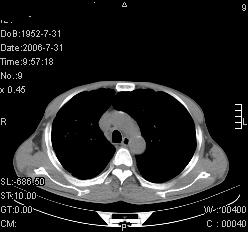

患者,男,54岁,咳嗦,咳痰20天。抗炎治疗2周。现esr76mm/h,目前患者症状明显好转,但发现两次ct片未见明显变化。两次分别做与7.25、7.31。第一次诊断右肺上叶炎症累计胸膜。大家看,从影像上内排除结核吗?

结核的可能性非常大,右上肺病变应该考虑干酪性肺炎。理由:

1.纵隔内多发淋巴结肿大。

2.esr76mm/h。

3.虽经抗炎治疗肺窗病灶有所吸收、减小,但纵隔窗病灶形态、密度、范围无明显变化。如果是单纯的大叶性肺炎,“抗炎治疗2周,目前患者症状明显好转”病灶应该基本消散了,至少也处于吸收消散期,密度变淡、范围变小。同时本病例所示其内的密度不均匀,见多发大小不一空洞样影也不符合大叶性肺炎吸收消散期表现。

病灶特点:片状 索条 结节混杂影,部分融合,密度不均,广泛累及相应胸膜.

临床治疗;二周未吸收.但症状好转.

多考虑:肺结核.